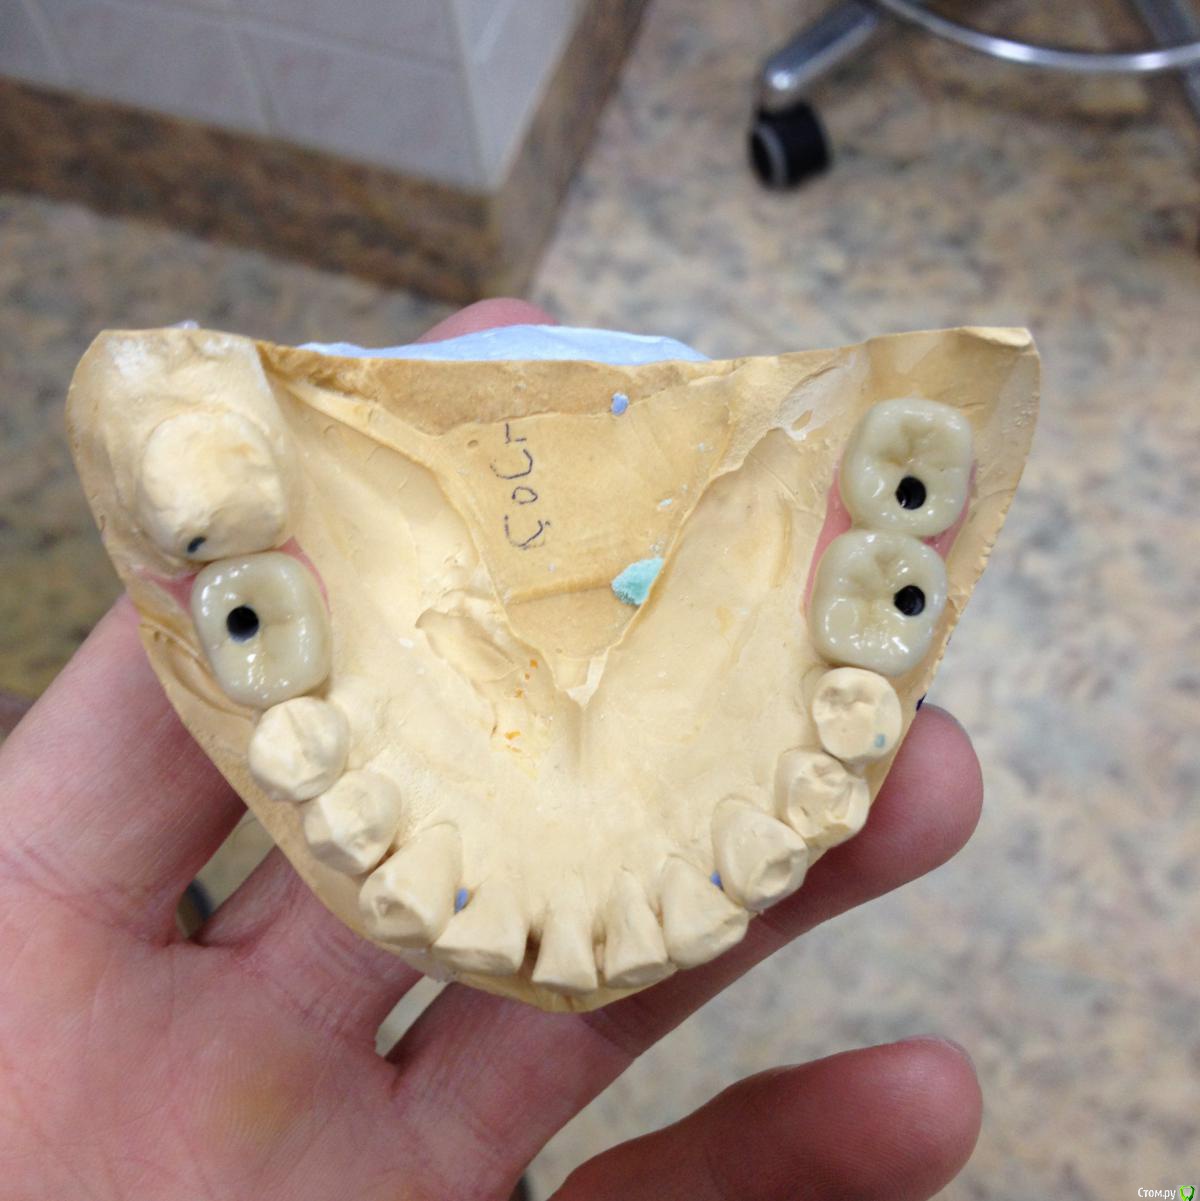

chervoncevdaniil Опубликовано 13 марта, 2016 Поделиться Опубликовано 13 марта, 2016 На фото,где вы меряете без керамики 36 и 37,почему 36 в контакте с антагонистом?Откуда место потом под облицовку взялось? Ссылка на комментарий

Shakirbura Опубликовано 13 марта, 2016 Автор Поделиться Опубликовано 13 марта, 2016 На фото,где вы меряете без керамики 36 и 37,почему 36 в контакте с антагонистом?Откуда место потом под облицовку взялось?Там контакта не было, но я техникам написал, чтоб места создали под керамику. Ну и регистрация прикуса повторная. Ссылка на комментарий

diesel87 Опубликовано 13 марта, 2016 Поделиться Опубликовано 13 марта, 2016 Есть фото окклюзионо? Почему 36 и 37 винтовая? Ссылка на комментарий

Shakirbura Опубликовано 13 марта, 2016 Автор Поделиться Опубликовано 13 марта, 2016 Есть фото окклюзионо? Почему 36 и 37 винтовая?Мне казалось винтовая предпочтительнее, я не прав? Ссылка на комментарий